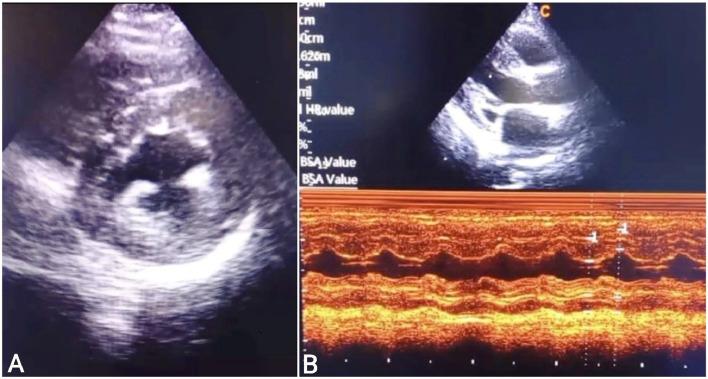

Complete heart block (CHB) is a disruption in electrical impulses to travel from atria to ventricles and can rarely be caused by myocardial bridging (MB), where cardiac tissue compresses a coronary artery during systole. The incidence of MB ranges from 0.5 % to 16 % in coronary angiography patients. This case report presents a 30-year-old female presented with dizziness, shortness of breath, and chest pain, diagnosed with third-degree AV block. Echocardiography revealed interventricular septal thickening and mild mitral regurgitation. Coronary angiography identified myocardial bridging in the mid LAD artery causing significant systolic stenosis. After ruling out reversible causes, a dual-chamber permanent pacemaker was implanted due to persistent heart block. The patient remained stable postprocedure, with decreasing cardiac biomarkers, and was discharged symptom-free with a follow-up appointment scheduled. MB can lead to serious cardiovascular events, including myocardial infarction and CHB. Clinicians must recognize the risks associated with MB and maintain a high suspicion for CHB to ensure timely management. Further studies are needed to clarify the CHB-MB relationship and improve patient outcomes.

摘要